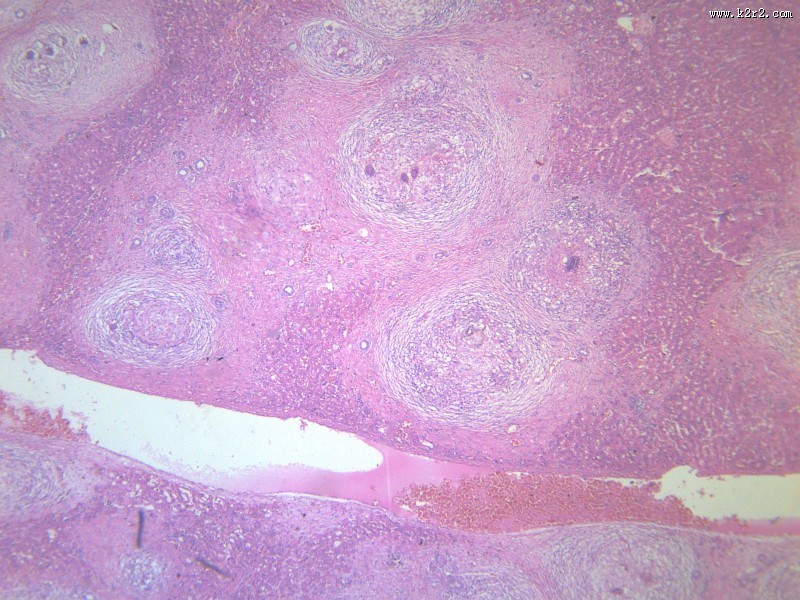

首页 > 其他类别 > 虫卵肉芽肿(12张) > 虫卵肉芽肿 第7张

虫卵肉芽肿 - 第7张